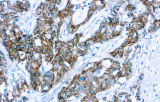

L’immunoistochimica (IHC) con anticorpi primari CE/IVD è essenziale per una diagnosi e classificazione accurata sia delle malignità ginecologiche che mammarie. Questi anticorpi consentono la rilevazione precisa di marcatori tumorali e proteine cellulari, supportando la diagnosi differenziale e guidando strategie terapeutiche personalizzate.

Studi recenti sottolineano il valore diagnostico delle proteine del complesso SWI/SNF, in particolare ARID1B, nell’identificazione di malignità ginecologiche dedifferenziate e indifferenziate – tumori aggressivi con prognosi sfavorevole. L’IHC di ARID1B offre alta specificità e viene sempre più integrata nei pannelli diagnostici per migliorare la precisione. Pannelli con marcatori aggiuntivi supportano anche la differenziazione dei sarcomi uterini, aumentando l’accuratezza diagnostica. Evidenze emergenti suggeriscono che ARID1B potrebbe rappresentare un potenziale bersaglio terapeutico nel carcinoma ovarico a cellule chiare, sebbene le applicazioni cliniche rimangano in fase di ricerca.